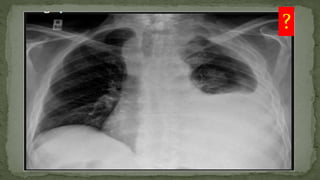

Consolidation Right

upper zone

?